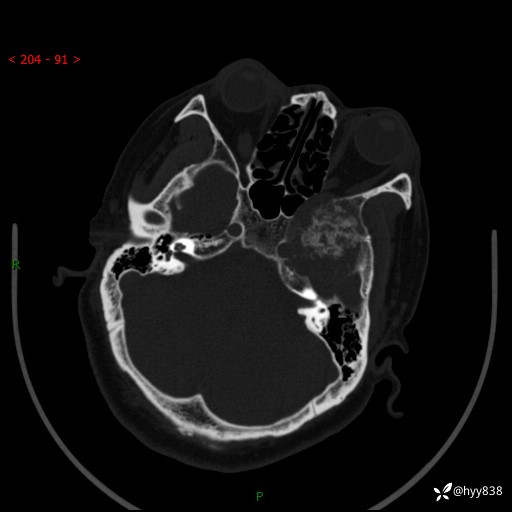

颅脑CT平扫